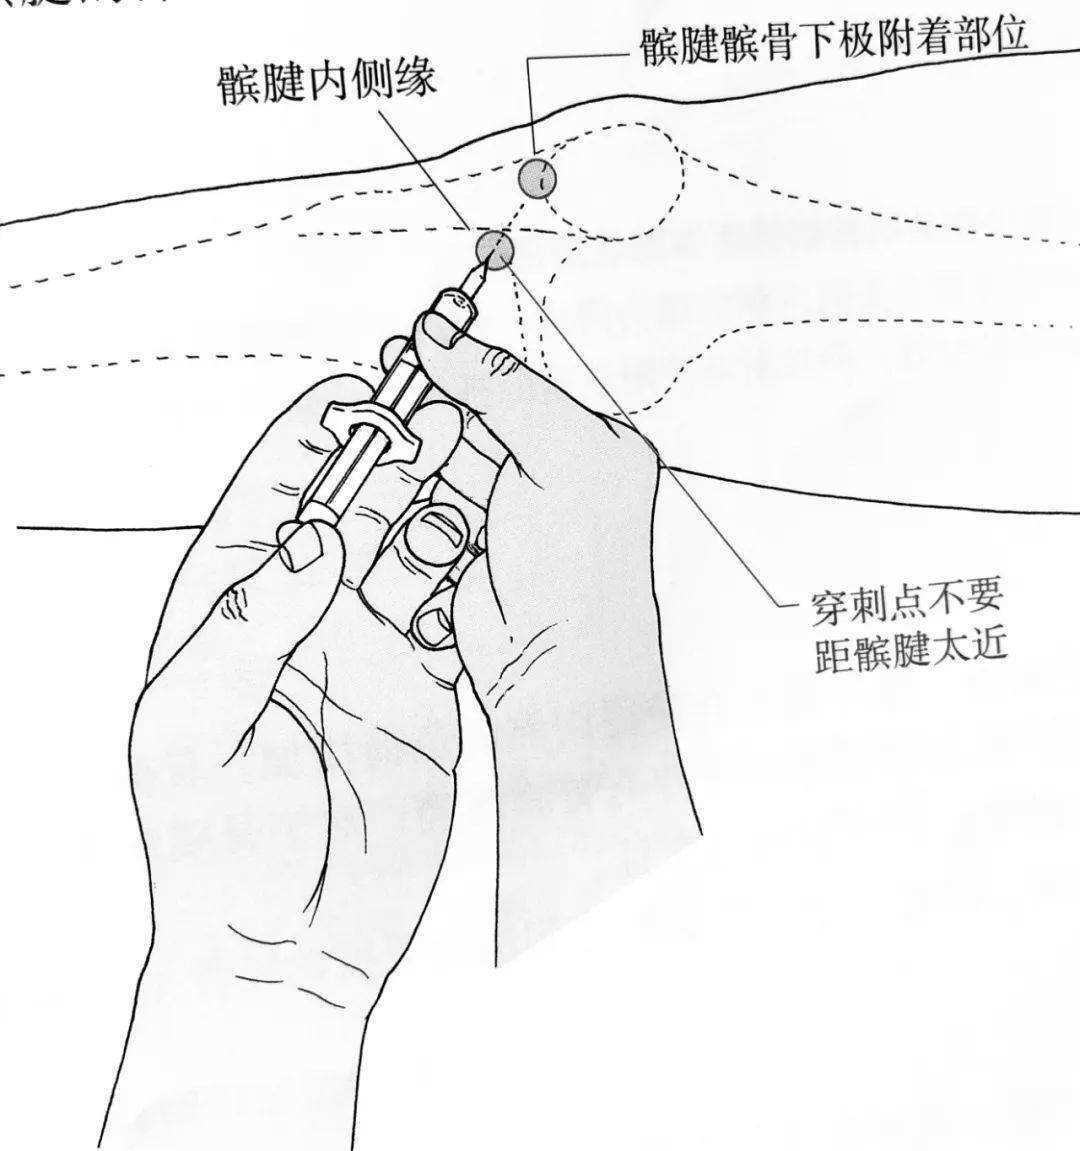

3.透明质酸钠注射液膝关节腔注射:透明质酸钠为膝关节腔关节液的主要成分,起到延缓关节软骨退变、修复及润滑作用,可改善炎症反应。关节内注射,1次25mg,1周1次,连续5周为一个疗程。

定位膝眼准确膝关节腔穿刺抽吸积液及玻璃酸钠注射